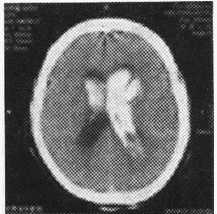

男,56岁。高血压病患者。旅游登山中突然右侧肢体发麻、乏力。急送医院,摄头颅CT片如下图。

(单选题)CT影像中描述病灶呈()

D:高密度区

第2题,共2个问题

(单选题)病损部位在()

D:右侧基底节区